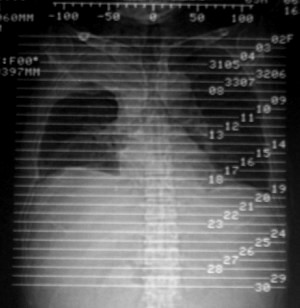

m ,60岁,右上肺ca术后一月。

纵隔淋巴结增大,双侧胸水。考虑术后残留,而非复发。

肺癌术后 。双侧胸水 纵隔 胸膜 肝脏转移